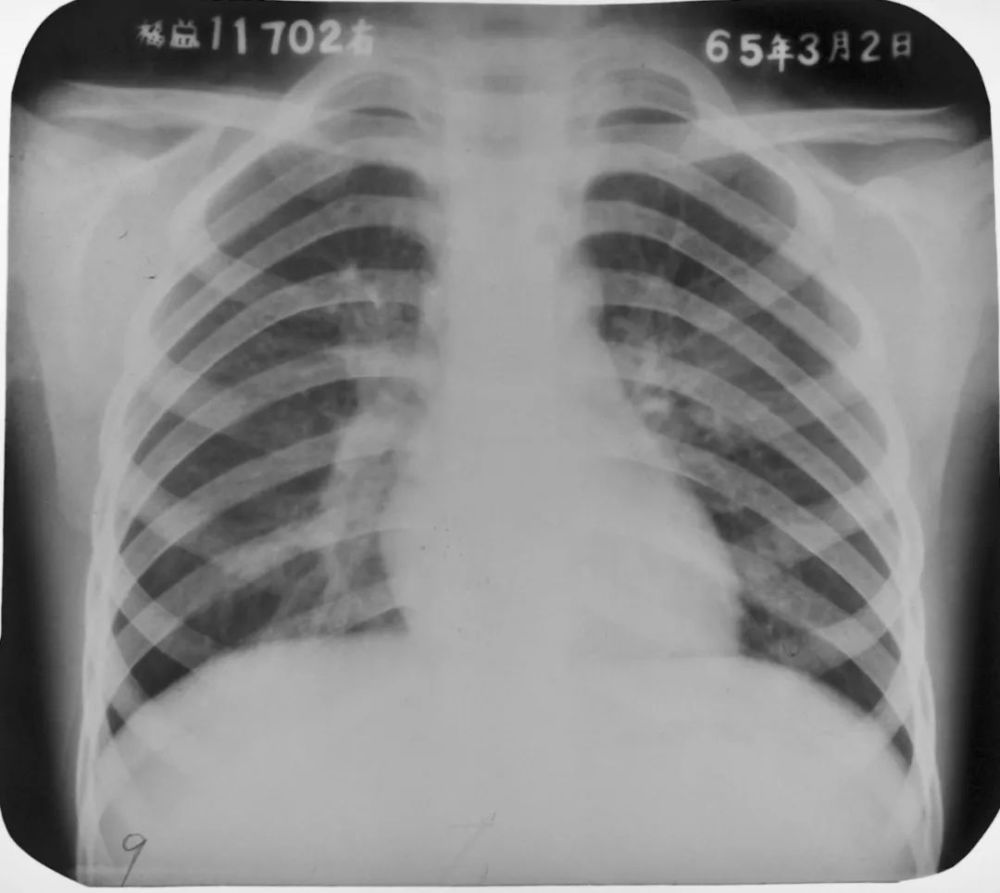

陳旧性肺結核 ちんきゅうせいはいけっかく 肺結核の中で治療により完治したものや自然治癒例です。

石灰化陰影 過去の肺の炎症などが治った場所に、カルシウム(石灰) が沈着した状態です。